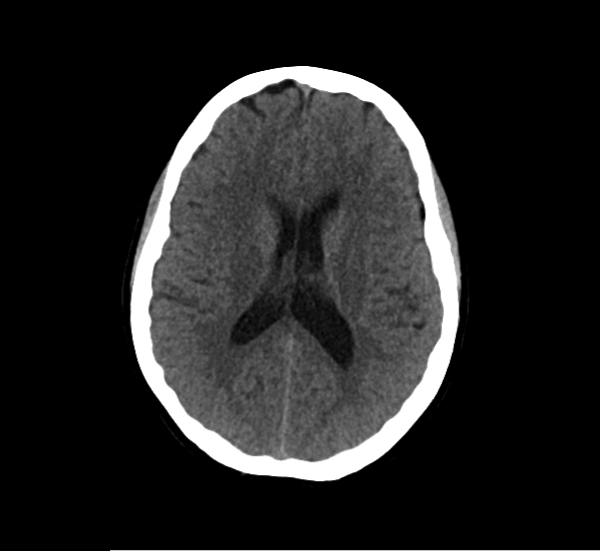

CT Brain Anatomy